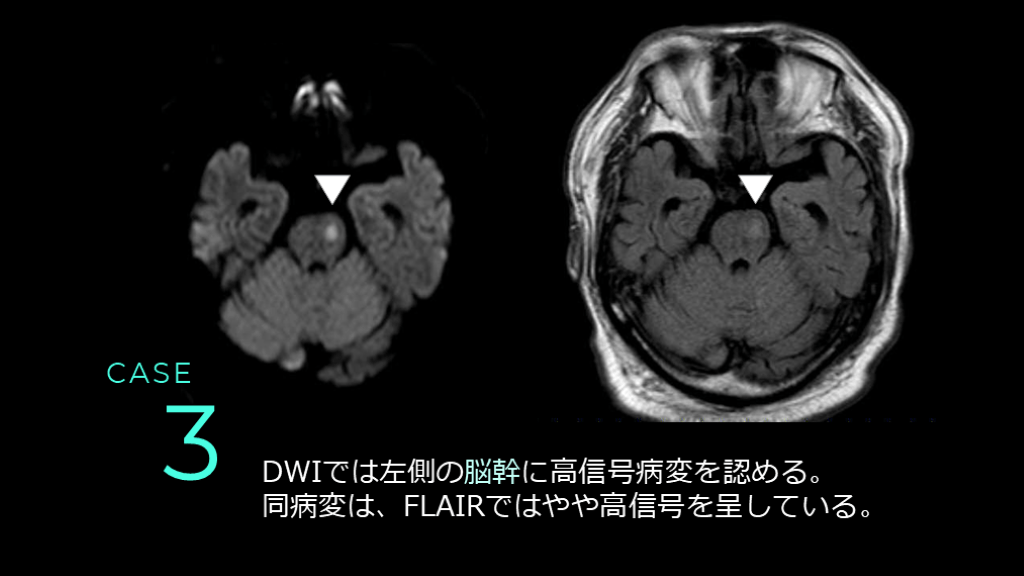

CASE 3 DWI FLAIR T2*

CASE 3 DWIでは左側の脳幹に高信号病変を認める。 同病変は、FLAIRではやや高信号を呈している。

#50.

CASE 3 MRAでは前方循環系はICAの口径不整が認められる。 後方循環系は、左のVAが右より細く描出されている。

CASE 3 コメント: 脳幹のラクナ梗塞。DWI HIGHでFLAIRもHIGHなので、やや時間のたった病変であることがポイントです。 なお、左VAは先天的な低形成と推測されます。